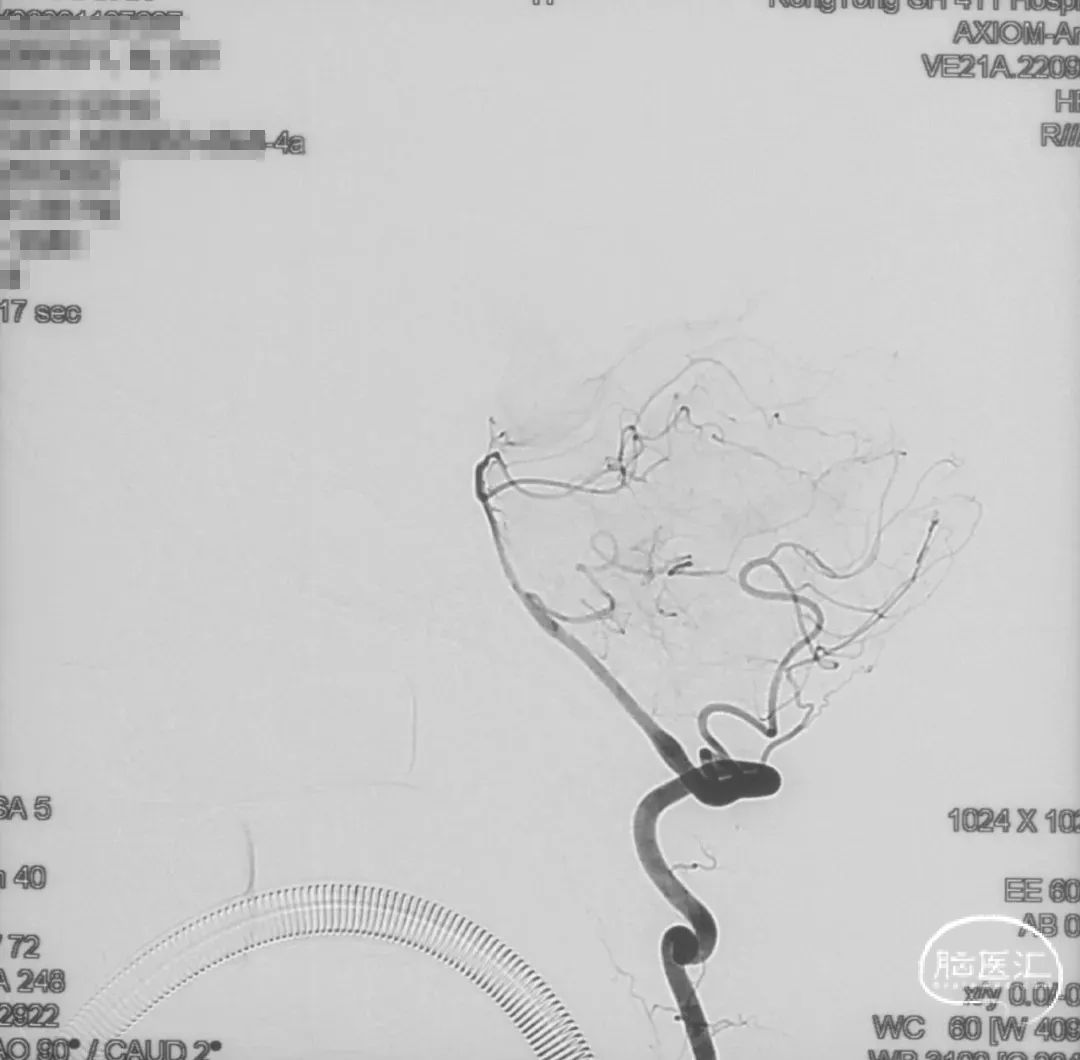

术前造影

证实为TDAVF,为岩上窦型。R-ECA正侧位见右侧脑膜中动脉分支、枕动脉分支、颞浅动脉分支向瘘口供血,经幕上迂曲扩张的静脉、中脑周围静脉、基底静脉向深部静脉引流。

R-ICA正侧位见右侧脑膜垂体干向瘘口供血

L-ICA正侧位见左侧脑膜垂体干分支向瘘口供血

L-ECA正侧位未见向瘘口供血

L-VA、R-VA正侧位右侧小脑上动脉脑膜支向瘘口供血

结构分析:右侧天幕区硬脑膜动静脉瘘,瘘口位于右侧岩上窦,供血动脉主要包括右侧脑膜中动脉的颞支、岩鳞支,右侧枕动脉分支,右侧颞浅动脉分支,双侧脑膜垂体干,右侧小脑上动脉脑膜支,经幕上迂曲扩张的静脉、中脑周围静脉、基底静脉向深部静脉引流,引流静脉起始部见扩张的静脉球。Cognard分型IV型,Borden分型III型,Lawton分型IV型(岩上窦型)。